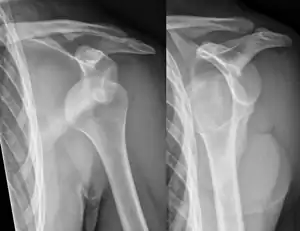

Lightbulb sign indicative of posterior shoulder dislocation shown on the left. On the right, the same shoulder after reduction.